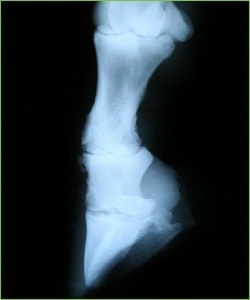

Jei žirgas nešlubuoja, deja, tai dar nereiškia, kad jo kojos sveikos. „Nelygus“ bėgimas, po pertraukos užstingę sąnariai, tinstančios kojos, netaisyklinga stovėsena ir kiti panašūs simptomai gali reikšti rimtus pažeidimus. Laimei, kojų problemoms diagnozuoti yra puiki, tik nepelnytai ignoruojama priemonė – rentgenas. Nepasikliaukite vien savo akimis – jos šioje situacijoje bevertės. Žirgai yra talentingi skausmo ir problemų maskuotojai. Jie gali apgauti net ir žymiai labiau patyrusius specialistus. Patikėkite, ne vienam veterinarijos gydytojui teko išgyventi didžiulę nuostabą, pamačius žvalaus ir „beveik nešlubo“ žirgo kojų vaizdą rentgeno nuotraukoje, atskleidusioje gilias, su judėjimu beveik nesuderinamas problemas.

Taigi, jei planuojate žirgą joti, būtinai padarykite kojų nuotraukas - be jų nežinosite realios padėties ir negalėsite suplanuoti teisingo krūvio.

„Nalyvas“ – ties čiurna esantis neišnykstantis patinimas. Kalbant medicinos terminais, tai - lėtinis sausgyslės ir aplink ją esančių raiščių bei audinių uždegimas, dėl kurio uždegiminis skystis suteka į žemiausią sausgyslės makšties vietą ir ten pasilieka, vėliau sustandėja. „Nalyvai“ – labai aiškus signalas: šitas žirgas turi problemų su sausgyslėmis! Neteisingi krūviai ir/arba neteisingas kanopos balansas sausgyslėse sukėlė įvairias mikro traumas ir pažeidimus, kurie buvo tik apgydyti arba išvis pražiūrėti. Išoriškai problemos tarsi ir nematyti, bet tokios sausgyslės visam laikui išliks silpnesnės, tad nenustebkite, jei santykinai nesunki trauma žirgą tiesiogine prasme išvers iš kojų.

Raiščiai - tai elastingas lygiagrečių skaidulų pluoštas, jungiantis kaulą su kaulu. Jų traumas sukelia panašios priežastys kaip ir sausgyslių ar sąnarių traumas. Jų gijimo trukmė irgi labai ilga. Be to, lėtinių pažeidimų veikiami raiščiai ima kaulėti. Tai labai skausminga, neišgydoma ir dažnesnė, nei įsivaizduojate, problema.

Kojų gydymo „kaina“: rentgeno nuotrauka - apie 40 Lt. Visų kojų ištyrimui gali prireikti iki 16-18 nuotraukų, nes probleminę vietą gali tekti apžiūrėti keliais skirtingais kampais. Gydymo arba skausmo mažinimo kaina gali siekti nuo kelių šimtų iki kelių tūkstančių litų.